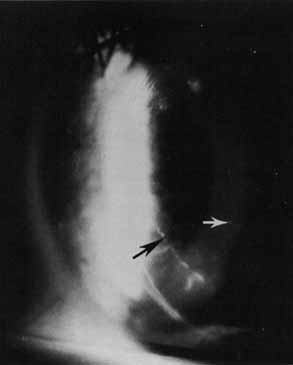

Fig. 9 Visual results of suture-fixated posterior chamber lenses during penetrating keratoplasty. Using a BVIOO-4 Ethicon needle, two prolene sutures are placed through the midperipheral iris, one at approximately 3 o'clock and one at 9 o'clock. Each suture also passes through one hole in the optic of the intraocular lens with the knots being tied between the iris and the anterior surface of the optic. The haptics of the lens are positioned at 3 o'clock and 9 o'clock within the ciliary sulcus. (From Price FW Jr, Whitson WE: Visual results of suture-fixated posterior chamber lenses during penetrating keratotomy. Ophthalmology 96:1234, 1989, with permission)